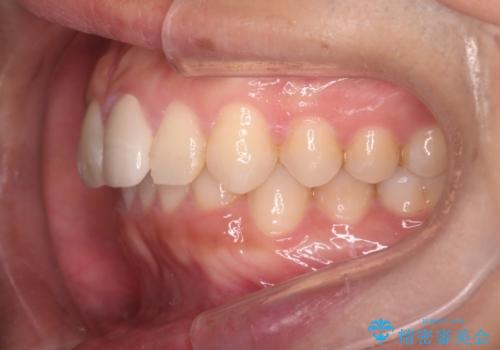

インビザラインにて治療を行うことで、前歯のがたつきが改善されました。

左上1番目の前歯はセラミックをご希望されたので、セラミックにて被せ物の治療を行いました。

とても綺麗な前歯になりました。